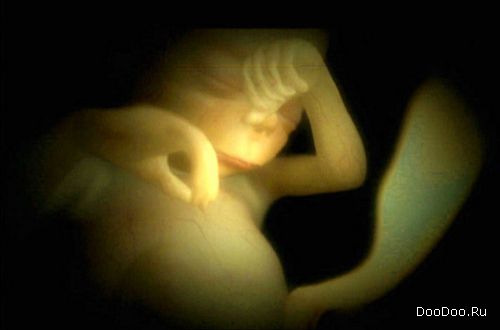

Восемь недель. Этот зародыш в состоянии пинаться и двигать ручками вверх и вниз.

Зародыш мягко перемещается в матке.